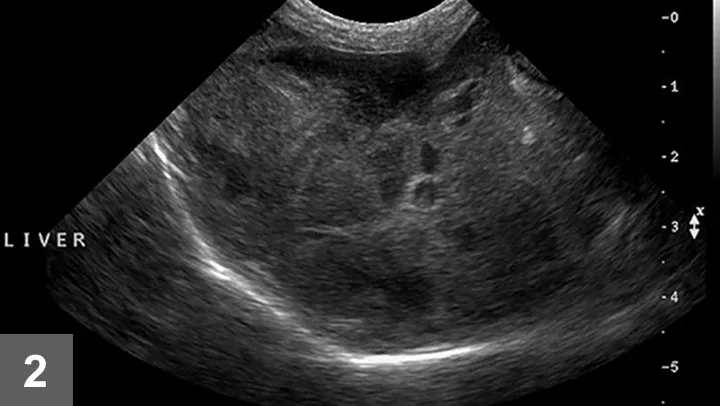

• Liver tissue should be submitted for histopathologic evaluation (Figure 3).

• In addition to standard hematoxylin and eosin, a variety of additional stains can be used, such as Fouchet’s, Masson’s trichrome, periodic acid-Schiff, Perl’s Prussian Blue iron stain, reticulin, rubeanic acid, and rhodanine.

• Unfixed liver tissue can also be submitted for quantitative copper analysis. Note that formalin-fixed tissue is not appropriate.

Microscopic view of a tissue sample showing multiple circular structures, likely follicles, surrounded by a pink-stained matrix. Black arrows indicate areas of interest, highlighting cellular features relevant to veterinary pathology.

FIGURE 3 Histopathology sample obtained at laparotomy that demonstrates regenerative nodules (wide arrows) and fibrosis (thin arrows), both of which are indicative of cirrhosis. Hematoxylin and eosin stain; 40× magnification.